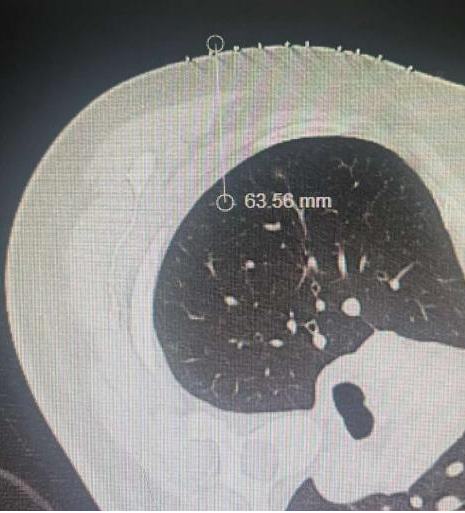

梁恒星教授预先准备好定位装置,用一根10厘米长的定位针对右上肺结节进行了准确的定位,整个定位时间仅为20分钟。在手术室完成麻醉后,梁恒星教授团队对患者进行全胸腔镜下右中肺叶切除+右上肺结节切除。快速冰冻切片结果回报明确了梁恒星教授的术前判断,因此团队对患者进行了系统淋巴结清扫,为赵女士彻底解除了后顾之忧。整个手术仅耗时2个小时,手术切口不到一根拇指长。48小时后,赵女士拔除了引流管并能下床自由活动,术后第5天顺利出院。

由于结节位置特殊,团队利用CT定位后对上肺结节进行精准切除